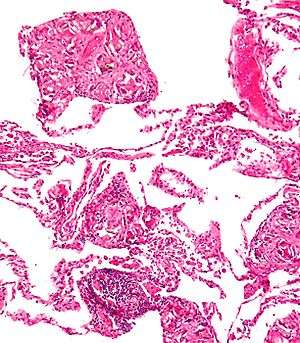

Foreign body granuloma

The foreign body granuloma is a response of biological tissue to any foreign material in the tissue.[1] Tissue-encapsulation of an implant is part of this. An infection around a splinter is part of this, too.[2]

The presence of the implant changes the healing response, and this is called the foreign-body reaction (FBR). FBR consists of: protein adsorption, macrophages, multinucleated foreign body giant cells (macrophage fusion), fibroblasts, and angiogenesis.